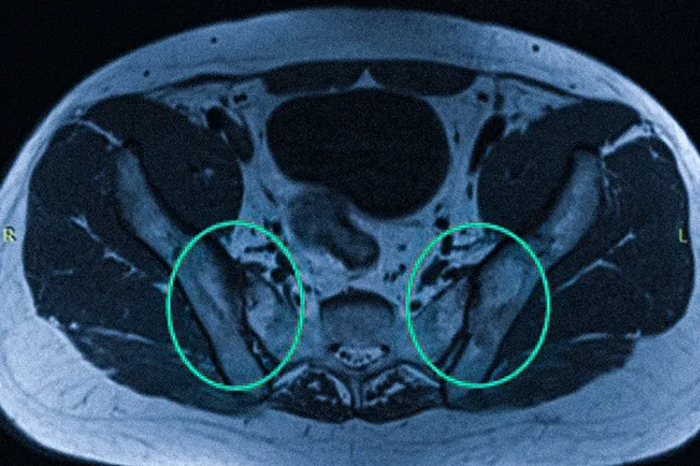

На сериях послойных изображений, выполненных в различных проекциях через район крестца и таза, визуализируются КПС, их поверхности, хрящи, полости, рядом прилегающие связки вместе с сухожилиями, включая кости таза. Медицинский персонал в ходе расшифровки данных изучает заболевания, выявленные при МРТ, признаки воспалений, сужения щелей суставов, а также присутствие выпота в суставную полость.

В определенном протоколе диагностики врач может выявить признаки сакроилеита в форме отечности костного мозга. Применение контрастного реагента при МРТ помогает оценить динамику его скопления и вывода из тканей. На снимках проводят исключение грубых деформаций по типу новообразований разного генеза, остеомиелита, остеопороза и других заболеваний. Результаты исследования вносятся в документацию и выдаются на руки пациенту.